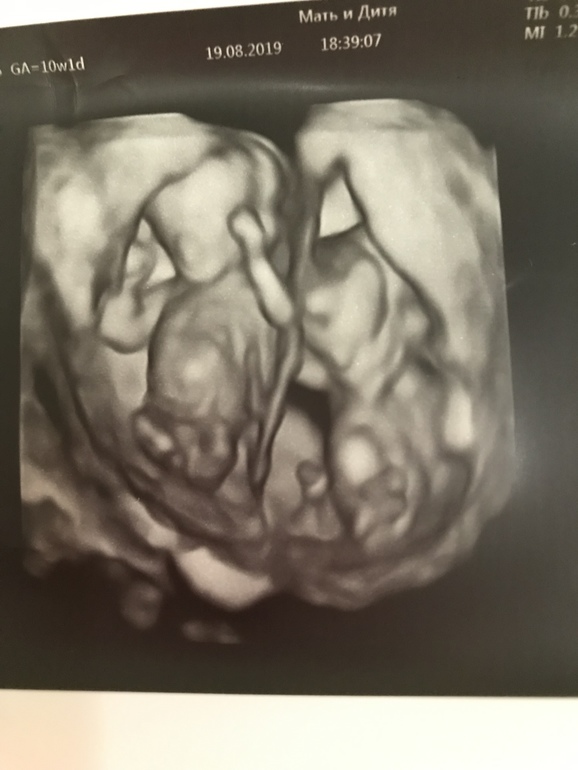

Всё о нашей беременностиКакими нервами мне дался этот скрининг, а точнее их было, 2 просто не передать словами. На скрининг по направлению меня записала мой гинеколог. Потом Клиника поменяла врача, и я после отзывов переживала. Но собрав волю в кулак с широченной улыбкой помчалась на приём. Радость моя длилась не особо долго. Врач действительно была не особо приветлива, а даже прямо таки совсем не приветлива. Но это не так важно решила я. Но вот как только я легла началось самое интересное: мне вручили листок и ручку, чтобы я записала все данные, что скажет врач, причём листок-был моим направлением от врача, который просто сложили в несколько раз. Только начала делать «Здесь что, их двое?». Ну да, двое. В направлении все было написано. И тут началось «да вам на два времени надо записываться! Это что за безответственность, сейчас я ошибусь потом виновата буду». К слову, я потом написала своему врачу, меня записывали на 2 времени, но, видимо, уже их Клиника при переносе записи оставила только одно окно. В общем минут 5 я слушала какая я плохая и безответственная и времени совсем нет, так как у неё на меня и так было 10 минут. Я выслушала это молча, все-таки настрой мой трудно было сбить. Все её данные я записывала. На чсс второго малыша, я спросила могу я увидеть детей, на что мне ответили, что нет времени искать подходящий ракурс. Ну ок, это я тоже как-то проглотила. И тут я спрашиваю «с малышами все хорошо?» на что получила ответ «вам все расскажет ваш лечащий врач». Я немножко офигела. Терплю. Мне дают штрихкоды на кровь и задают вопрос «а у вашего первого ребёнка есть отклонения?» я говорю, что нет, все хорошо и снова спрашиваю как там малыши на что уже получила в грубом тоне «я вам ясно дала понять, что все расскажит лечащий врач». Я не знала, что после скрининга нужно будет сдавать кровь и спросила в процедурном всем ли обычно дают направление на анализ, на что получила ответ «я не знаю». В общем что со мной творилось я описать не могу. Записалась сразу же в МиД на Севастопольском, так как была рядом, и вот уже оттуда мы с мужем и сыном выходили счастливыми с фото и видео наших парней 😊 Для меня было удивительно, что врач сама позвала мужа и сказала, что если я не против, позовёт сына. Мы смотрели 40-ка минутный онлайн фильм с нашими детьми, пересчитали все пальчики, посмотрели все органы! А главное услышали, что на данном сроке никаких патологий не выявлено!!! Кстати, по замерам в первой клинике КТР были 69 и 72, а в МиД 75 и 73.

На это можно смотреть вечно!